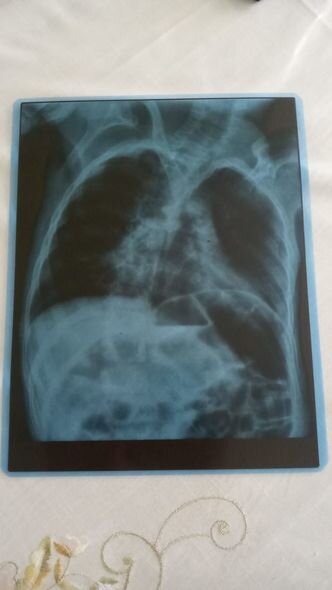

Nərminə Əzizova bildirib ki, Ömərə həm də pnevmoniya diaqnozu qoyulub.

"Öməri soyuq havalarda qətiyyən çölə çıxarmırıq. Qış ərzində ancaq evdə olur. Evin istisinə o qədər öyrəşir ki, çox az müddətə çölə çıxanda xəstələnir. Həkim Ömərə pnevmoniya diaqnozu qoyub. Ömər pnevmoniyaya görə dəfələrlə müalicə alsa da, böyük irəliləyiş olmayıb. Yardımsevər şəxslərin dəstəyi ilə onu həyatda saxlaya bilirik, müalicələrini edirik. Hazırda müalicələrin yarıda qalmaması üçün 150 manata ehtiyacımız var. Ömərin vəziyyəti ilə bağlı mən işləyə bilmirəm, ailəmizdə tək işləyən yoldaşımdır. Ömərdən başqa iki oğlum da var. İnanın, vəziyyətimiz çox ağırdır. Yardımsevər şəxslərdən mənim balama dəstək olmağı, onu bu yolda tək qoymamağı xahiş edirəm".